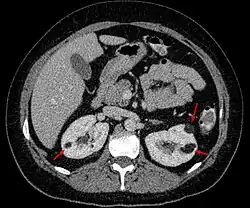

Examens d'imagerie

L'angiomyolipome est, dans la majorité des cas, une découverte de hasard lors d'un examen de l'abdomen par échographie, tomodensitométrie ou Imagerie par résonance magnétique.

- A l'échographie il apparaît hyper-échogène.

- A la tomodensitométrie sans injection de produit de contraste il est de densité négative (UH<0, tonalité graisseuse) et se rehausse instantanément après injection (riche vascularisation).